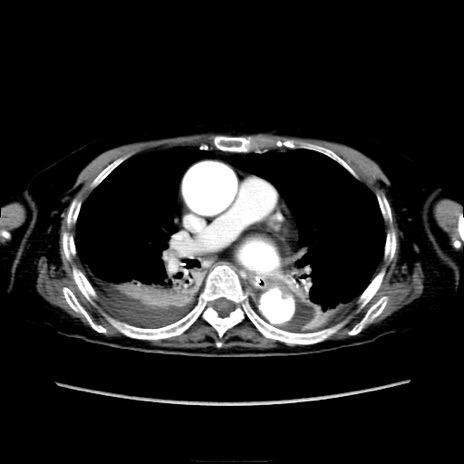

症例40(横断像)

【症例】90歳代女性

【主訴】腹痛・嘔吐

【現病歴】 食欲低下、嘔吐があり昨日他院受診。肺炎と診断され入院となる。入院後より腹部全体に圧痛あり。胃管留置され経過みていたが、症状持続するため、

当院転院となる。

【既往歴】胸椎圧迫骨折、胆石症

【身体所見】腹部:中央に激痛あり、圧痛あり、反跳痛不明

【データ】WBC 17100、CRP 18.82

他院CT

横断像